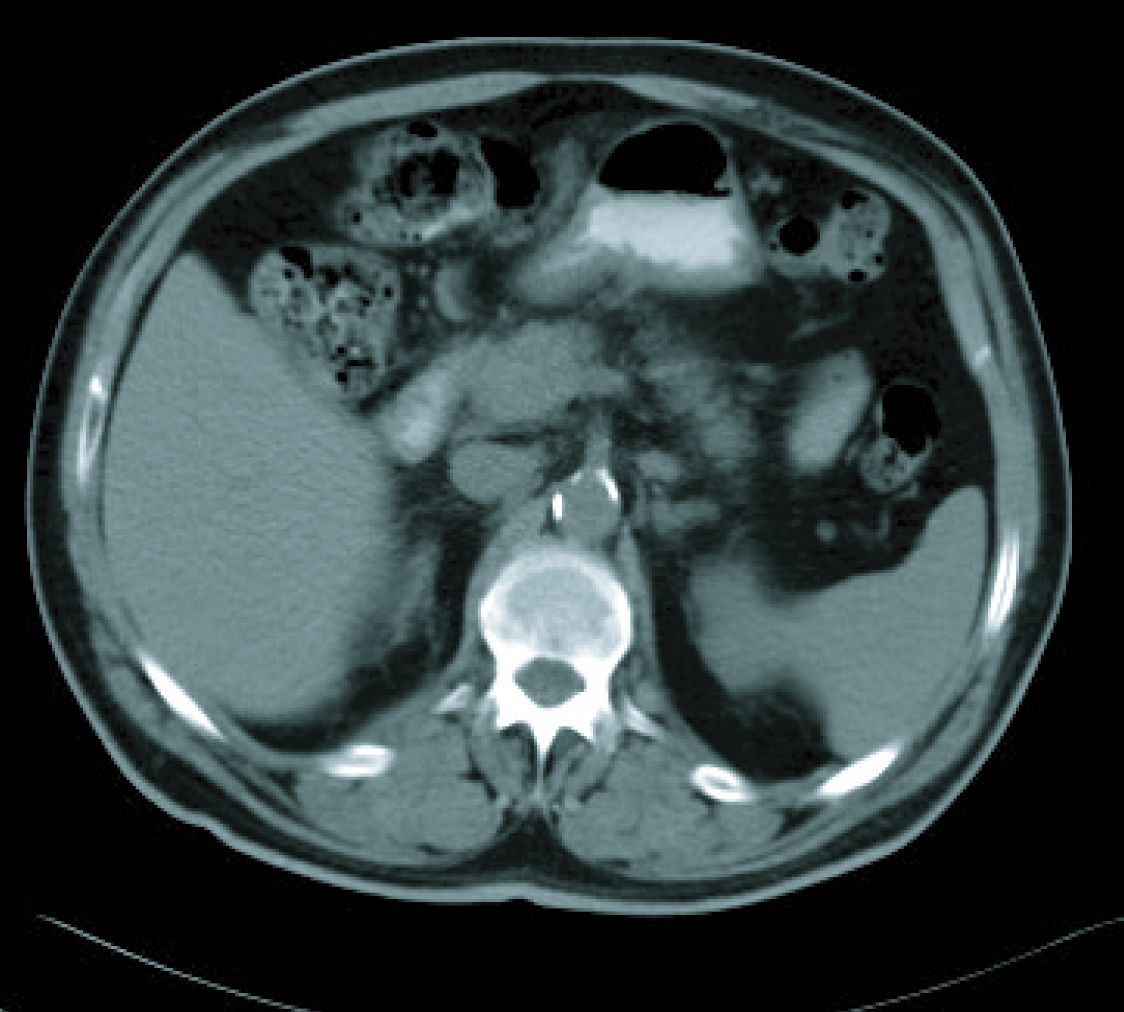

In a radiological re-assessment after the third treatment cycle, a significant reduction of adenopathies and gastric wall thickening was observed. Thus the response was re-evaluated as a partial remission, and after continuing for three more cycles of treatment, the radiological re-assessment maintained the same response (Fig. 3, 4). After the sixth treatment cycle was completed, the follow-up began. The patient continued with periodic evaluations, maintaining a good general state (ECOG 0) and a 14 kg weight gain since diagnosis. Follow-up CT scans showed that the radiological remission was maintained, and that there was a reduction of gastric wall thickening and normalisation of remote lymph nodes.

![]() Click for large image | Figure 3. CT imaging after 6 cicles. |

![]() Click for large image | Figure 4. CT imaging after 6 cicles. |